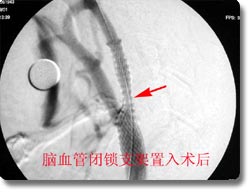

开展了脑动脉瘤、脑血管畸形、颈内动脉海绵窦瘘、脊髓血管畸形的神经介入治疗和恶性肿瘤的次选择性化疗,尤其是对巨大动脉瘤的栓塞成功率达到国内领先水平。同时开展了脑动脉瘤、动静脉畸形、高血压脑出血的手术治疗和血管闭塞性疾病的颅内外搭桥手术、颈内动脉内膜切除术、急性栓塞的溶栓治疗术、血管内支架放置手术,颅内动脉瘤电解可脱性螺旋圈(CDC)治疗,先后收治病人4000余例,积累了丰富的经验,为脑血管狭窄、脑供血不足及脑血栓病人的康复提供了有力保证。介入治疗具有不出血、无感染、损伤小、风险小、恢复快的优点,是脑血管疾病病人的理想选择。2003年,与北京宣武医院强强联合成立了北京市脑血管病中心重庆分中心。2005年成功地承办了第七届全国神经外科血管内治疗研讨会,受到了与会专家的一致赞誉。